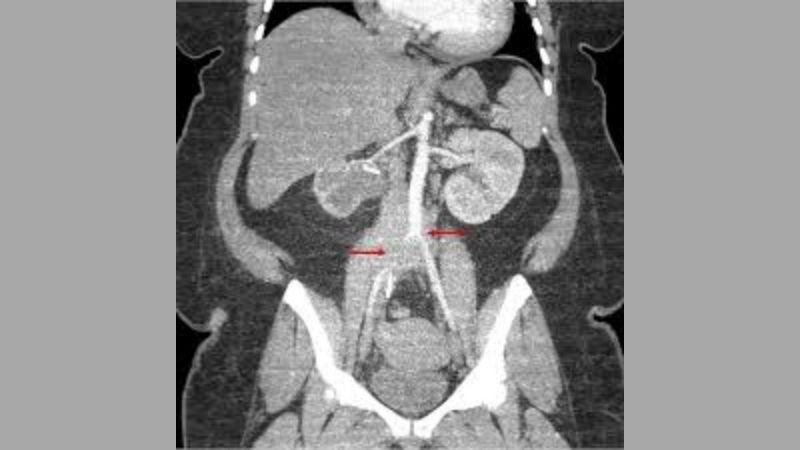

Aortitis diagnosis with advanced medical imaging

Aortic aneurysm as a complication of aortitis